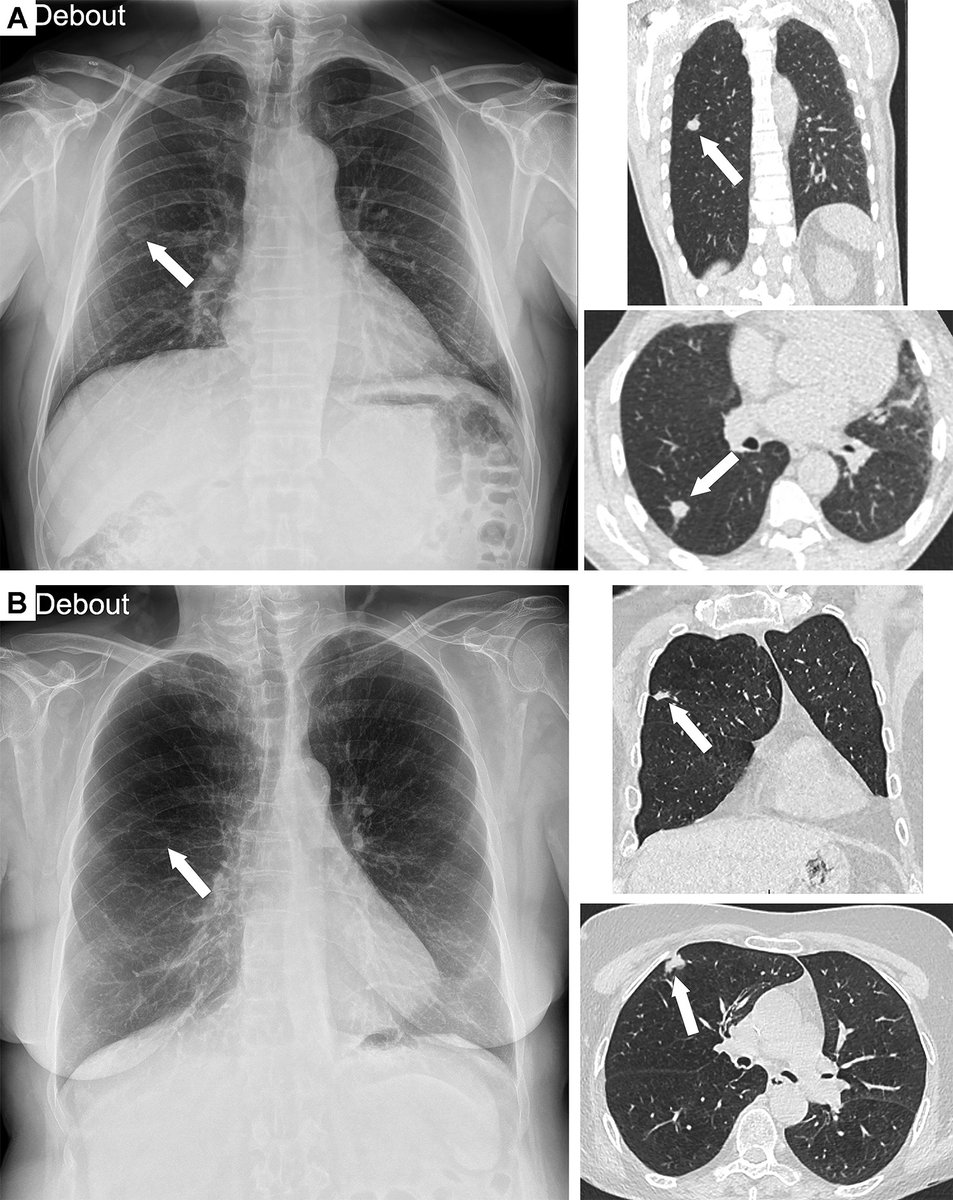

Despite the increasing use of CT and MRI, chest radiography remains the most performed radiologic examination worldwide. Read the full article, “Using AI to Improve Radiologist Performance in Detection of Abnormalities on Chest Radiographs” bit.ly/49EzdB5 Radiology

Despite the increasing use of CT and MRI, chest radiography remains the most performed radiologic examination worldwide. Read the full article, “Using AI to Improve Radiologist Performance in Detection of Abnormalities on Chest Radiographs” bit.ly/49EzdB5 <a href="/radiology_rsna/">Radiology</a>